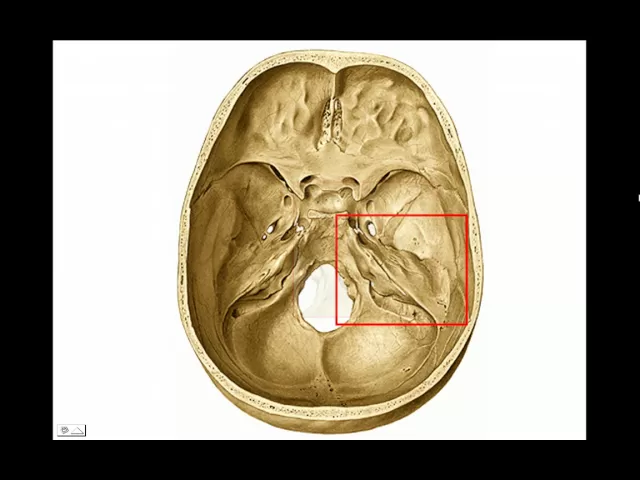

abajo no se ve desde exocraneo en la base se ve en la órbita Por qué Porque se dirige hacia delante por debajo de la hendidura esfenoidal va a dar paso al nervio maxilar superior hacia atrás y hacia fuera tenemos el agujero oval que da paso al nervio maxilar inferior y a la arteria mening menor y hacia atrás y hacia fuera de este casi pegaditos el agujero redondo menor que va a dar paso a la arteria mening media acá vemos una órbita vista de adelante lo ampliamos y acá se ve el agujero redondo mayor en la

órbita solamente desde exoco por debajo de la hendidura esfenoidal buenísimo por delante del penasco del temporal tenemos el agujero rasgado anterior que va a dar paso al nervio vidiano y por detrás entre el penasco del Temporal y el occipital el agujero rasgado posterior que va a estar eso es occipital eso es Peñasco va a estar dividido por un filete fibroso en dos compartimentos uno principal o posterior que da paso a la vena chular interna que está continuando al seno lateral el seno lateral se mete en este agujero rasgado posterior cambia de nombre y pasa a

llamarse vena jugular interna y también da paso al neumogástrico y al espinal y por delante pasan el seno petroso inferior que va a ir a desangrar a la vena sucular interna y el nervio gloso faring Si vemos el Peñasco visto desde arriba Vamos a encontrar en su cara postero superior el bueno en la antero superior empezamos por adelante una eminencia ovoidea que es la eminencia arcuata que pertenece al conducto semicircular superior por delante una placa cuadrilátera que es el tecmen timpani y por dentro de estas dos un orificio en forma de semiluna que corresponde a